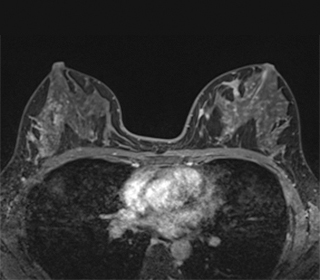

図4 MRI画像

マンモグラフィーや超音波検査で悪性が疑われる場合や、乳がんの拡がりを判断する必要がある時には、精密検査としてMRI検査(要予約)を行います。